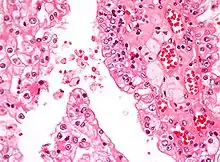

| Micrograph showing the most common type of kidney cancer (clear cell renal cell carcinoma). H&E stain. | |

The most common type of kidney malignancy is renal cell carcinoma,[33] which is thought to originate from cells in the proximal convoluted tubule of the nephron.[15][34] Another type of kidney cancer although less common, is transitional cell cancer (TCC) or urothelial carcinoma of the renal pelvis.[35] The renal pelvis is the part of the kidney that collects urine and drains it into a tube called the ureter.[35] The cells that line the renal pelvis are called transitional cells, and are also sometimes called urothelial cells. The transitional/urothelial cells in the renal pelvis are the same type of cells that line the ureter and bladder. For this reason TCC of the renal pelvis is distinct from RCC and is thought to behave more like bladder cancer.[35] Other rare types of kidney cancers that can arise from the urothelial cells of the renal pelvis are squamous cell carcinoma and adenocarcinoma.[15]